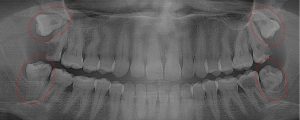

This 19 year old patient has all four 3rd molars present (circled). Only the upper left 3rd molar has fully erupted. The lower left 3rd molar is partially exposed and decaying while the lower right soft tissue impacted, both requiring extraction. Note the double crown on the upper right third molar.